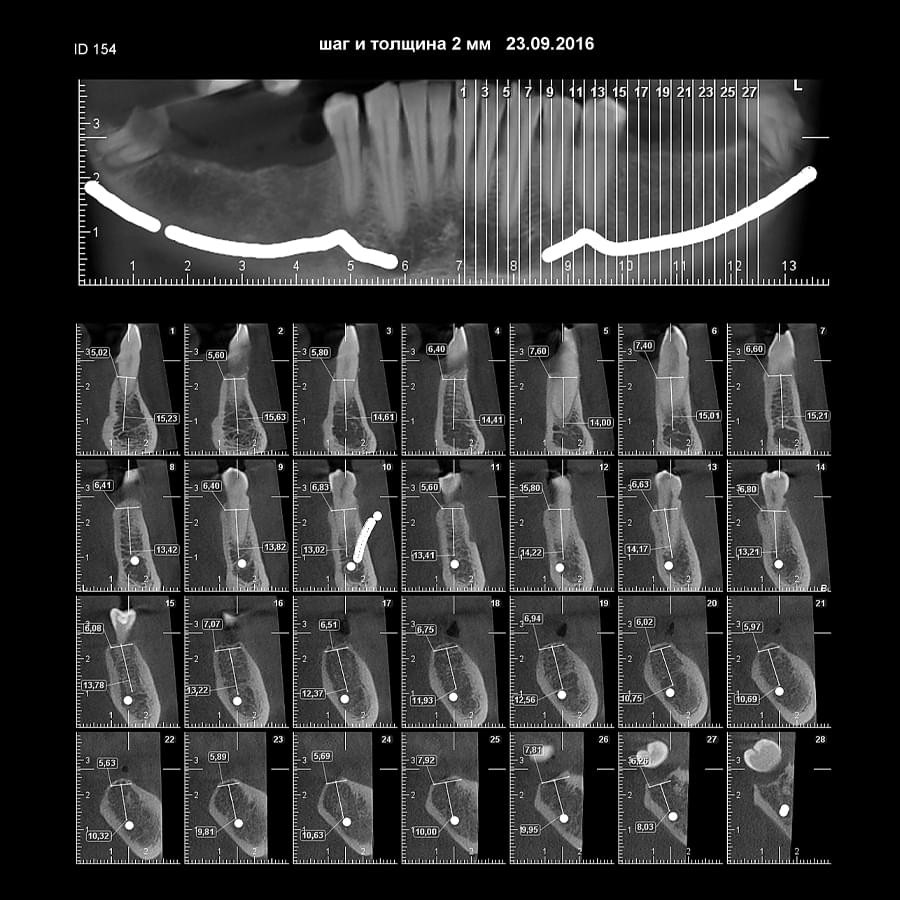

Успішна імплантація починається з бездоганної діагностики. Томограф PLANMECA забезпечує

зображення в реальному масштабі 1:1 без геометричних спотворень, що критично важливо для

вибору розміру та позиції імплантату.

Ми економимо ваш час, надаючи повний пакет передопераційної підготовки:

Детальна розмітка: промальовування нижньощелепного каналу, візуалізація синусів та

ментальних отворів.

Точні виміри: визначення висоти та ширини альвеолярного гребеня, а також оцінка щільності

кісткової тканини в зоні майбутньої операції.

Всі дослідження миттєво доступні у вашій персональній папці на нашому захищеному сервері —

ви можете відкрити їх на будь-якому комп’ютері для демонстрації пацієнту або планування

операції.